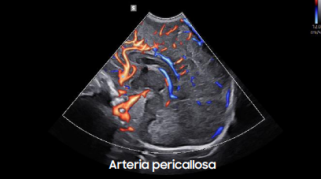

Galería de imágenes